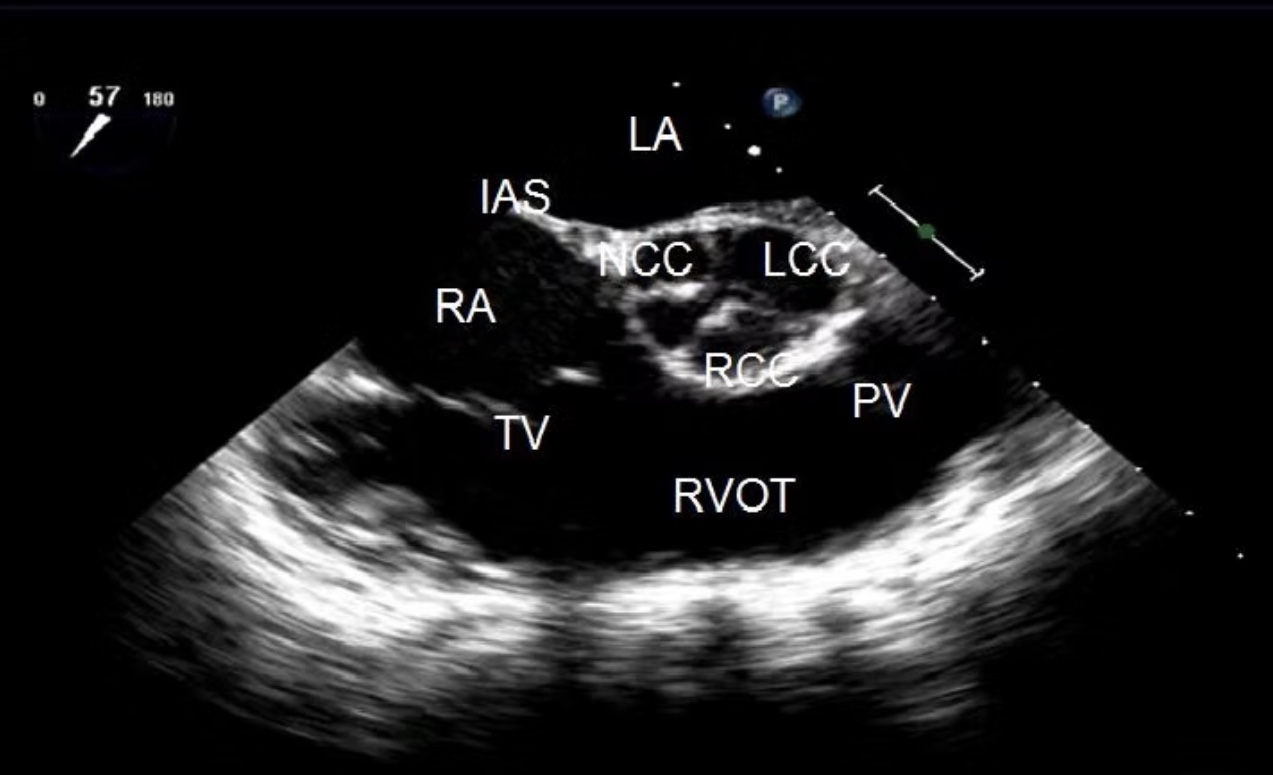

ME AV SAX

Identify the view and structures